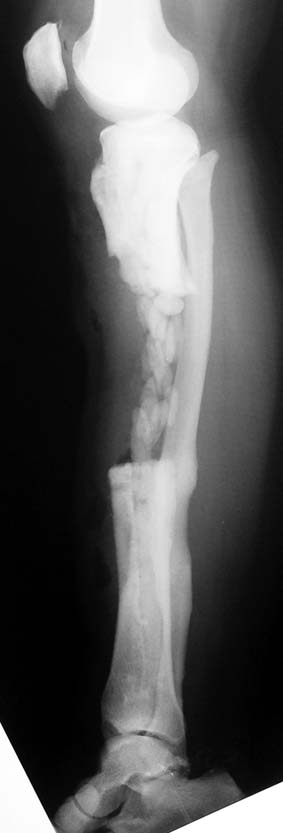

Uygun radikal debridman tüm nekrotik kemik ve yumuşak dokuların çıkartılmasını gerektirir, ve sıklıkla uzuvda instabiliteye neden olur. Kalan kemik ve yumuşak doku defektinin bir şekilde fiksasyonu ve rekonstrüksiyonu gereklidir. İlizarov’un ortaya koyduğu distraksiyon osteogenezi yöntemi, kaynamanın elde edilmesi, deformitenin düzeltilmesi, bacak boy eşitsizliğinin giderilmesi ve segmental defektlerin rekonstrükte edilmesi için başarıyla kullanılmaktadır.

Eksternal fiksatör ile geçen süre (eksternal fiksasyon indeksi), gereken distraksiyon miktarına bağlıdır ve bu süre boyunca bazı komplikasyonlarla karşılaşılabilir. Distraksiyon dönemi sona erdikten sonra, distraksiyon süresinin iki katını aşan konsolidasyon döneminde hastalar eksternal fiksatörü zorlukla tolere edebilirler. Yeterli konsolidasyon sağlanmadan eksternal fiksatör çıkartılırsa ise kırıklar, deformite ve kısalık oluşabilir. Hastanın fiksatör ile birlikte geçirdiği sürenin azaltılması ve böylece hasta konforunun ve aktivite düzeyinin arttırılması için intramedüller çivi üzerinden uzatma yöntemi uygulanmaktadır. Bu yöntemde distraksiyon dönemi sona erdiğinde kemiğin içindeki çivi statik olarak kilitlenmekte ve eksternal fiksatör çıkartılmaktadır. Stabilizasyon intramedüller çivi tarafından sağlandıktan sonra konsolidasyon dönemi gerçekleşmektedir. Bu şekilde hem eksternal fiksatörün uzun süre kalmasından hem de erken çıkartılmasından kaynaklanan komplikasyonların önüne geçilmektedir.